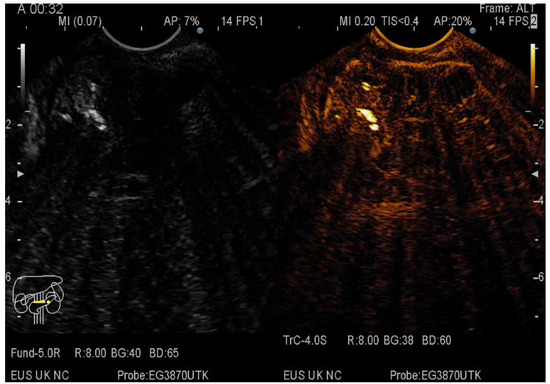

2.5. CE-EUS Procedure

3.2. EUS-FNA/FNB + CE-EUS of Solid Pancreatic Lesions Subgroup

3.3. EUS-FNA/FNB + CE-EUS of Pancreatic Cystic Lesions Subgroup